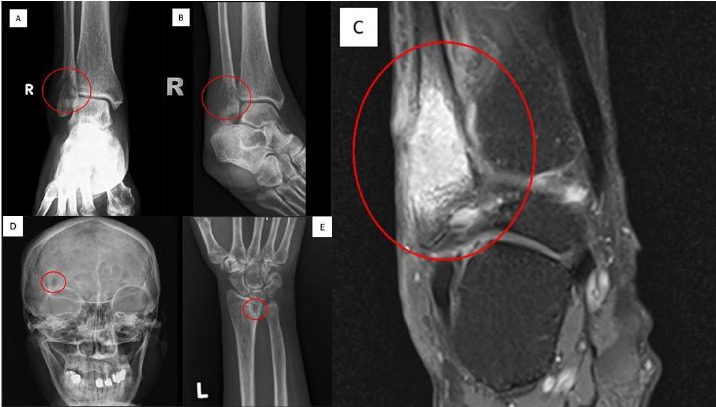

We report the case of a 54-year-old woman with poorly controlled type 2 diabetes mellitus, dyslipidaemia, hypertension and a 3-month history of fixed cutaneous sporotrichosis treated with itraconazole 200 mg once daily. She subsequently presented with progressive enlarging nodular lesions on her left forearm, wrist and right forehead, with right ankle pain. Imaging revealed multifocal osseous involvement, including small lucent lesions in the right frontal bone and left distal radius and aggressive lesions in the right ankle and left radius. MRI of the right ankle showed an enhancing lesion in the distal fibula with cortical destruction. A biopsy showed chronic suppurative granulomatous inflammation, and a fungal culture grew Sporothrix spp. The patient underwent surgical debridement of the ankle and was continued on itraconazole for 1 year. She had complete resolution of all her lesions, resulting in no residual functional disabilities observed during follow-up.

我们报告一例54岁女性,患有控制不良的2型糖尿病,血脂异常,高血压和3个月的固定皮肤孢子虫病病史,伊曲康唑200mg,每日1次。患者随后表现为左前臂、手腕和右前额渐进性增大的结节性病变,并伴有右踝关节疼痛。影像学显示多灶性骨受累,包括右额骨和左桡骨远端小病变,右踝关节和左桡骨侵袭性病变。右踝关节MRI显示腓骨远端强化病变伴皮质破坏。活检显示慢性化脓性肉芽肿性炎症,真菌培养生长孢子丝菌。患者接受了踝关节手术清创,并继续服用伊曲康唑1年。她的所有病变完全消退,随访期间没有观察到残留的功能障碍。